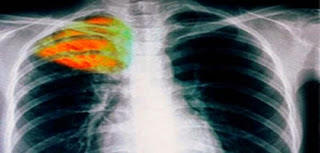

Η φυματίωση (TB)

είναι μια από τις κορυφαίες 10 αιτίες θανάτου παγκοσμίως.